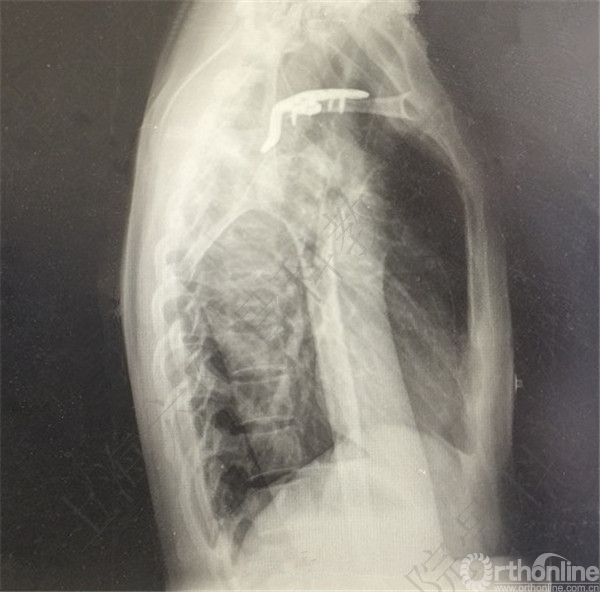

患者术后复查,X线摄片示:骨折端对位对线欠佳,远端骨块向前下方移位。

患者取出内固定,X线摄片示,骨折端畸形愈合,对位对线欠佳。

医方在复查期间未注意X线摄片显示的远端骨折移位,行取出内固定术前未充分告知患者。医方存在漏诊,手术指证掌握不当,术后并发症观察、处理不当,告知缺陷等过失。